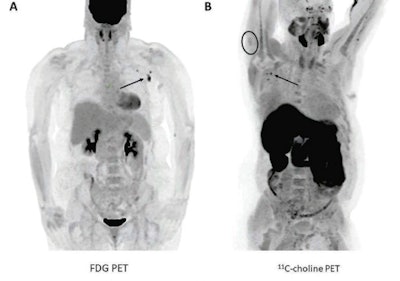

(A) A 57-year-old woman with right upper arm melanoma who received the first dose of the COVID-19 vaccine (Pfizer-BioNTech) in the left deltoid 15 days prior to FDG PET/CT. FDG uptake is observed within left axillary lymph nodes (arrow, SUVmax = 9.3). (B) A 62-year-old man with metastatic prostate carcinoma who received the second dose of COVID-19 vaccine (Pfizer-BioNTech) in the right deltoid seven days prior to C-11 choline PET/CT. Image courtesy of the American Journal of Roentgenology."We did not observe any PET-positive axillary lymph nodes beyond 24 days after vaccination. Thus, waiting 3-4 weeks after vaccination before undergoing PET examination for initial oncologic evaluation may also be reasonable, particularly in patients at greater risk of axillary nodal disease," the authors wrote.

Researchers at the Mayo Clinic in Rochester, MN, compared PET scans of patients before and after they received Pfizer-BioNTech or Moderna COVID-19 vaccinations and observed increased FDG and carbon-11 (C-11) choline uptake by axillary lymph nodes and ipsilateral deltoids. There had been no visible axillary node uptake prior to the vaccinations.

The researchers observed positive axillary lymph node uptake in 10.4% (7/67) of patients on FDG-PET examinations and 23.1% (3/13) of patients who underwent C-11 choline PET imaging. Ipsilateral deltoid uptake was present in 14.5% (8/55) of patients with documented injection laterality, including in 42.9% (3/7) of patients with positive axillary lymph nodes.